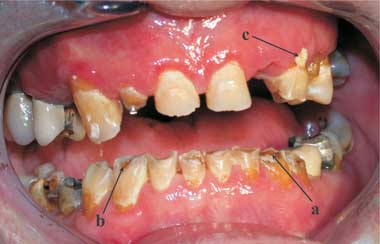

Intraoral examination revealed rampant dental caries (a), enamel erosion (b) and generalised calculus deposits (c).

A 22-year-old man presented with badly decayed teeth and generalised dental pain. Intraoral examination revealed rampant dental caries, enamel erosion and generalised calculus deposits (Box). The patient had a 2-year history of daily use of crystal methamphetamine, administered intravenously or via snorting. He complained of a dry mouth, which led him to consume 2–3 litres of carbonated beverages a day, and reported periods of jaw clenching and temporomandibular joint discomfort on waking.